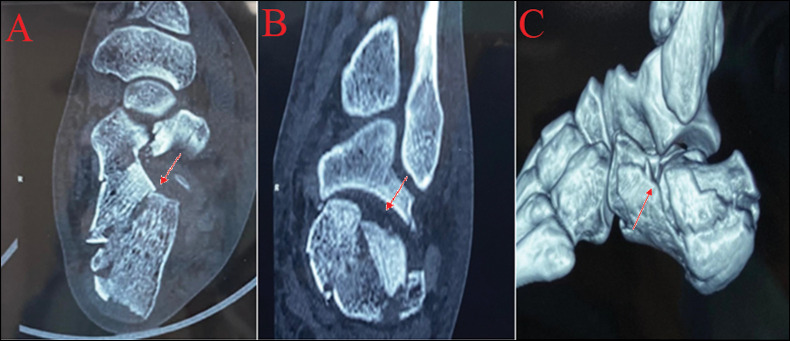

Materials and methods: Thirty-two patients (40 ft) with displaced intra-articular calcaneus fractures (10 were of Sanders type II, 16 were of type III, and 14 were of type IV) were treated between January 2018 and September 2021. All patients were managed surgically with open reduction and internal fixation using lateral extensile approach combined with de-roofing of the lateral wall. All patients were followed up for ≥1 year using functional parameters American Orthopaedic Foot and Ankle Score (AOFAS), visual analogue scale (VAS) and radiological parameters (Bohler angle, Gissane angle, height of the calcaneus, width of the calcaneus and pitch of calcaneus).

Results: Out of 32 patients, one patient lost to follow-up. At 1 year follow-up, mean AOFAS hindfoot score was 86.2 ± 5 (Sanders type II: 91.2, Sanders type III: 87.6, and Sanders type III: 81.4), mean VAS score was 91.3 ± 2.1, mean Bohler angle (°) was 27.2 ± 4.7, mean Gissane angle (°) was 136.4 ± 5.2, mean calcaneus height was 46.2 ± 2.1 mm and mean calcaneus width was 45.1 ± 3.2 mm. Patients with decreased Bohler angle between postoperative images and follow-up had lower AOFAS hindfoot scores. Complications included persistent swelling (64.10%), stiffness (33.33%), superficial infections (5.12%), and wound dehiscence (10.25%).

Conclusion: Lateral wall de-roofing is a useful technique which allows the lateral wall to get flattened reducing soft tissue complications and providing bone graft as well. This approach also adequately exposes fracture fragments, subtalar and calcaneocuboid joints for good anatomical reduction. Hence, it can act as a useful adjunct in the internal fixation of intra-articular calcaneus fractures.